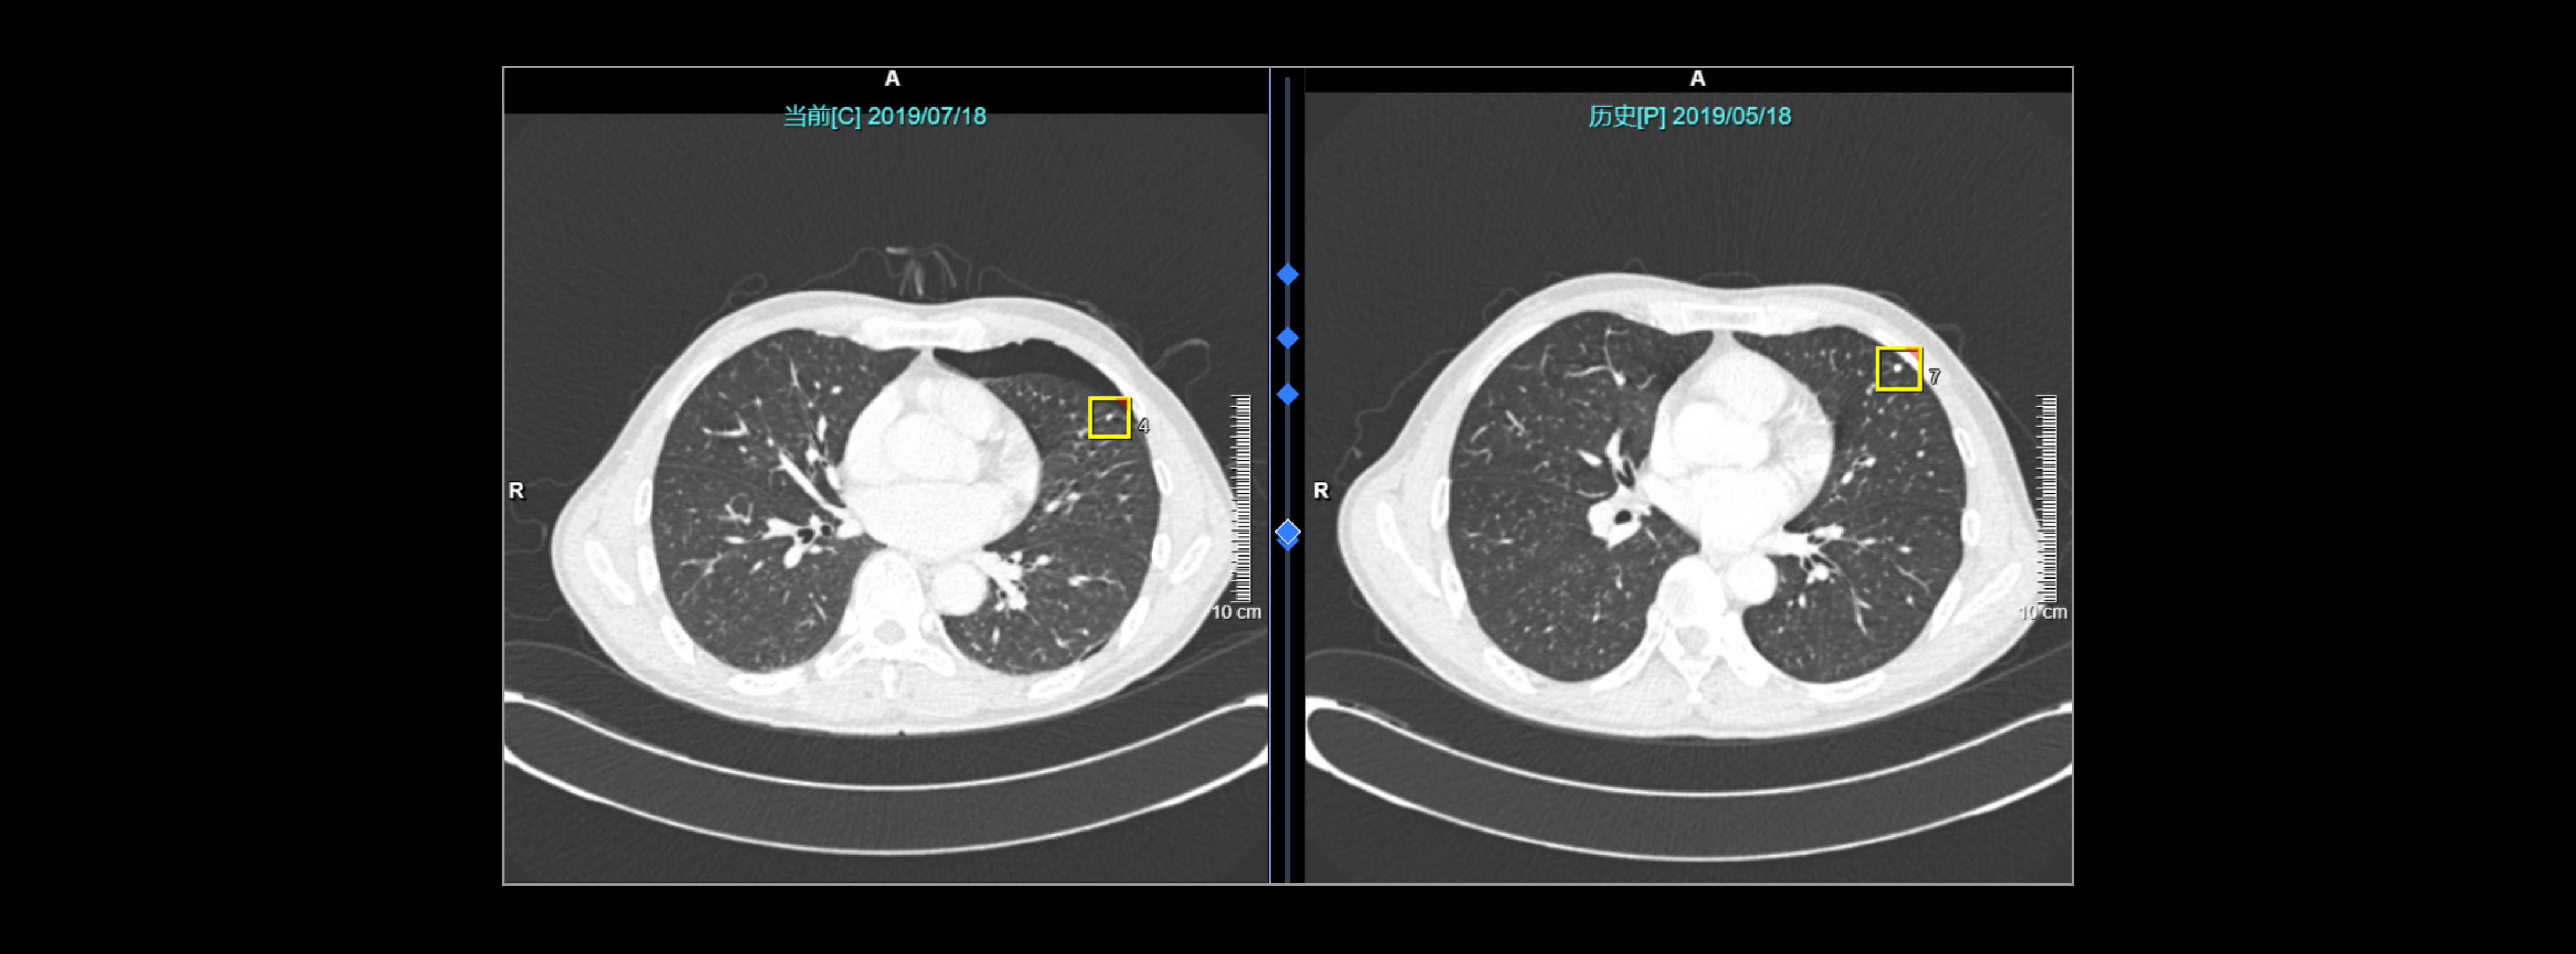

AI显示结节体积增大,且倍增时间符合肿瘤生长特性,病理结果为浸润性腺癌

肺结节随访分析助力浸润性腺癌诊断

解剖发生变化仍可实现精确图像配准与结节关联匹配